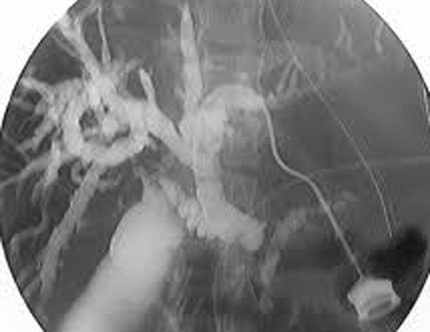

- Cholangiographie

transhepatique per cutanee : La cholagiographie

trans-hepatique est une radiographie des voies biliaires en

injectant directement dans le voie biliaire un produit de

contrast radio-opaque . Cela est possible nul que si elles

sont dilatees . La technique soit realise par une perfusion et

une injecte de calmant ,et anesthesie locale .Voie

d'abord est sur la ligne axilaire mediane ,au dessous de cul-de

sac pleural et dirige en direction vers le col de la 11e

cote . , on injecte le produit de contrast hydrosoluble et

prend les cliches imediatements . On peut utilisee le guide

de aiguille pour instalee une petite catheter pour drainage

la bile qui est en bloquee par un obstacle

. Technique se donne des images tres net des voies

biliaires intrahepatique i

Par une aiguille avec catheter place

a une des branche de voie biliaire le produit de

contrast a injecte suffisament pour opacifie

de tous le voie biliaire |

Image radiologique de voie

biliaire intrahepatique dilate . La vesicukle

biliaire , le canl cystique et canal choledoque sont

en vue nette . Cholagiographie per cutanee |